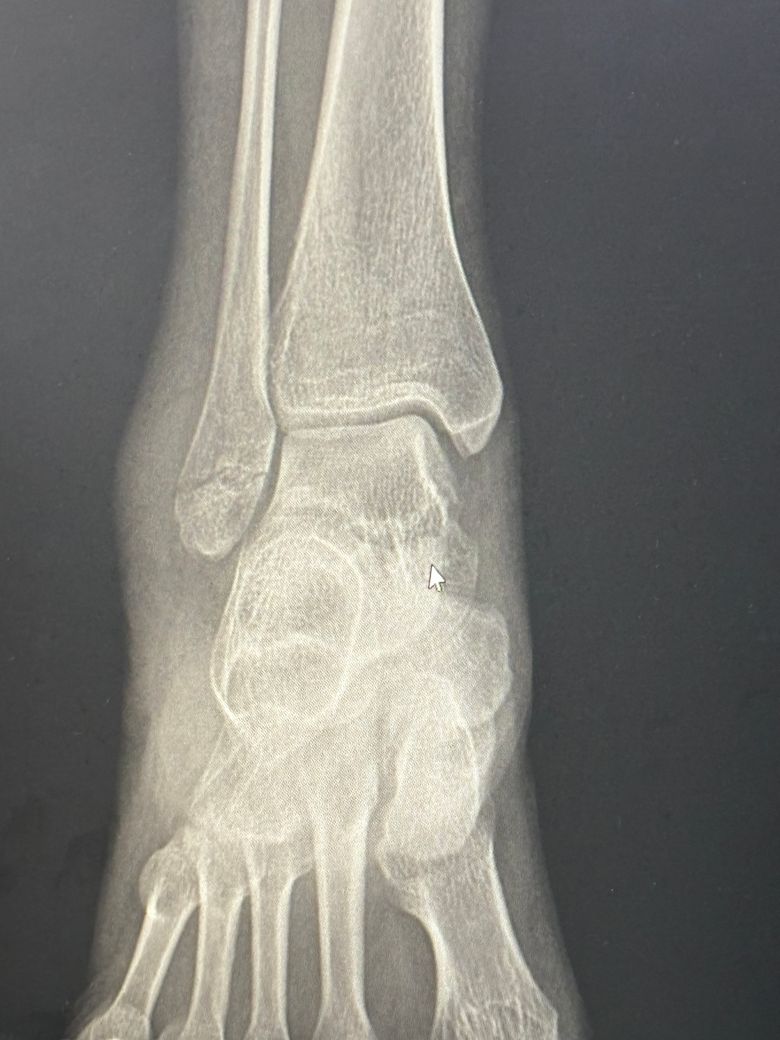

우측 외복사골 골절 수술 비수술 여부 궁금합니다

넘어져서 우측 외복사골이 골절되었습니다 엑스레이 첨부 합니다 ㅜㅜ 해당부위는 많이 움직이는 부위여서 수술을 해야한다고 하시는데 대학병원 파업중이라 개인병원에서만 진단 받아봐서 비수술도 가능할지 여쭤봅니다

• 2번 째 사진

외복사골 골절은 뼈의 어긋남 정도와 관절면 손상 여부에 따라 수술 여부가 결정됩니다. 엑스레이상 골절부위가 벌어져 있거나 관절면까지 영향을 주면 수술이 권장됩니다. 미세 골절이거나 정렬이 잘 유지되면 비수술적 치료도 가능합니다 정확한 판단인 정밀 진단을 받는 것이 필요하고 전문 병원을 방문하시는 것이 좋아요!